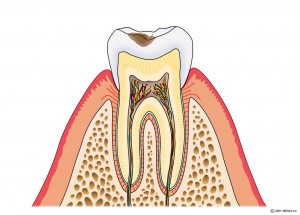

エナメル質に達するむし歯

光重合レジン充填・他

象牙質に達するむし歯

光重合レジン充填・部分的な詰め物(型どりを要す物)

歯髄に達するむし歯

歯の神経を取ります→土台を立てます→被せものをつくります。

CO:初期むし歯

C1:エナメル質に達するむし歯

C2:象牙質に達するむし歯

C3:歯髄に達するむし歯